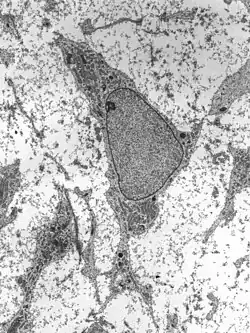

As células-tronco ou células estaminais são células que permanecem indiferenciadas, ou seja, ainda não passaram pelo processo de diferenciação celular. Podemos definir célula estaminal como uma célula que, quando se divide, produz uma célula que retém esse caráter indiferenciado e uma segunda célula que pode sofrer diferenciação.[1] Com isso, vemos que uma célula estaminal tem o potencial de se renovar a cada divisão, enquanto também produz uma célula nova capaz de responder ao seu ambiente, diferenciando-se de maneira particular (esse potencial nem sempre se verifica: algumas células-tronco dividem-se simetricamente, de modo que ambas as suas novas permanecem células estaminais).[1] Algumas células-tronco adultas são capazes de se diferenciar em mais de um tipo celular, como as células-tronco mesenquimais e as células-tronco hematopoiéticas, enquanto outras são consideradas precursoras diretas das células do tecido em que são encontradas, como as células-tronco da pele ou as células-tronco gonadais.

Uma célula estaminal tem uma extensa capacidade de proliferação, criando mais células estaminais (utilizada para manutenção de um devido organismo, pois garante uma autorrenovação constante, como, por exemplo, as células sanguíneas) e criando descendentes celulares diferentes.[2] As células estaminais são um conjunto embrionário de células que se mantêm mesmo em organismos adultos.[2] Células-tronco embrionárias são aquelas encontradas no embrião com até 4 a 5 dias de idade e têm a capacidade de formar todos os tipos celulares de um organismo adulto. Uma característica fundamental das células-tronco embrionárias é que elas podem ser mantidas (no corpo ou numa placa de cultivo) indefinidamente. O fato de uma única célula-tronco ser capaz de formar quase qualquer tipo de célula abre espaço para o uso dessas células como forma de experimentação para curar doenças ou regenerar tecidos danificados, como ocorre no ramo da ciência chamado engenharia de tecidos.

- Embrionárias – São encontradas no embrião humano no estado de blastocisto[3] e são classificadas como pluripotentes, devido ao seu poder de diferenciação celular de outros tecidos e por possuírem alta capacidade de proliferação. São as células estaminais com a mais ampla capacidade de diferenciação, pois sua diferenciação leva à origem de todos os tipos de células diferenciadas de um tecido adulto.[10]